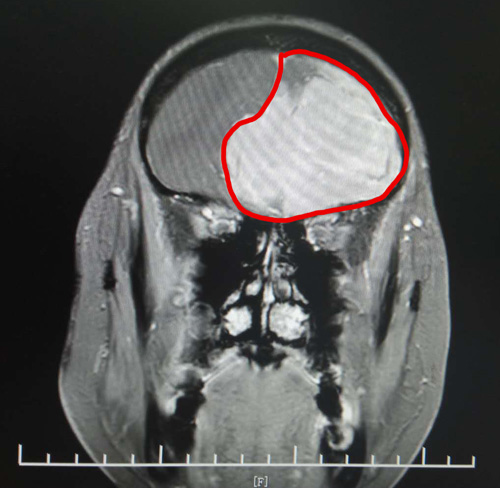

头颅MRI增强显示,丁阿姨的前颅窝有巨大的团块状异常信号。肿瘤大小约为6.9×5.6×5.4厘米,其大小与鸭蛋接近。

头颅MRI影像清晰显示了巨大的脑膜瘤

由于巨大肿瘤压迫患者不少重要的神经,肿瘤已将周围正常脑组织结构和主要脑供血动脉挤压得严重变形,手术难度很大。

在将大出血风险显著降低后,沈建康教授亲自主刀,为丁阿姨进行了肿瘤切除。手术中可以清楚看到,这个体积巨大的肿瘤已跨过中线,侵入患者的右侧额叶颅底。沈教授的手术刀一次次精准避开细小的血管和神经,将肿瘤分块全部切除。历时近4小时,手术取得了圆满成功。术后,丁阿姨很快恢复清醒,在医护人员和家人的精心照料下,身体状况恢复较好。